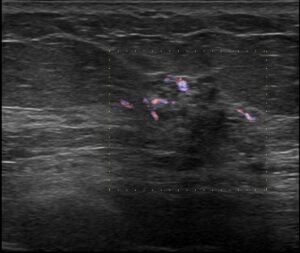

血流シグナルも認めます

点状高エコー+低エコー域+小嚢胞が確認出来て、

血流シグナルとエラストグラフィーの歪み低下が見えるから

DCIS以上と考えて…

乳癌か?と考えたら、低エコーの具合がそんなに黒くない(もっと低エコーが私の乳癌のイメージです。あくまで私のイメージ)からDCISかなぁ…なんて思いつつ